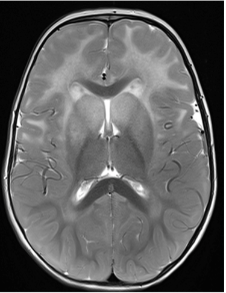

A radiologic diagnosis of Alexander disease is based on the presence of 4 out of 5 MRI features, which are most commonly observed in people with earlier age of onset (ie, infants and young children)1,15,16:

- Frontally predominant white matter changes1

- Periventricular rim abnormalities (eg, high T1-weighted signal and low T2-weighted signal)1

- Abnormalities of the basal ganglia and thalami1